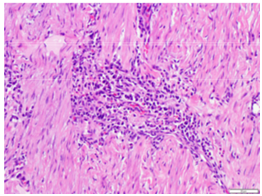

The entire strictured area was submitted for microscopic analysis. These sections showed chronic inflammation, crypt architectural distortion, and marked submucosal fibrosis with a multifocal lymphoplasmacytic infiltrate (Figure 1 & 2). No neoplasm was identified. Immunohistochemical stains for IgG (Figure 3) and IgG4 (Figure 4) were performed that highlighted foci of lymphoplasmacytic aggregates and many IgG4 positive plasma cells within the fibrotic areas. The histologic and immunophenotypic evidence supported the diagnosis of IgG4 related enteropathy in this patient.

Figure 2 Microscopic analysis of strictured area containing marked submucosal fibrosis with a multifocal lymphoplasmacytic infiltrate.